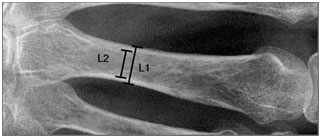

ΑΚΤΙΝΟΛΟΓΙΚΗ ΕΙΚΟΝΑ

Σε περιπτώσεις ήπιας αραχνοδακτυλίας, ο μετακαρπικός δείκτης (metacarpal index) προσδιορίζεται διαιρώντας το μήκος κάθε ενός από τα τελευταία τέσσερα μετακάρπια με το πλάτος του μέσου της φάλαγγας και υπολογίζοντας τον μέσο όρο. Οι ασθενείς με σύνδρομο Marfan έχουν συνήθως μετακαρπικό δείκτη >8.4, ενώ τα φυσιολογικά άτομα, <8. Άλλες σκελετικές εκδηλώσεις περιλαμβάνουν υψηλή υπερώα, μακρύ πρόσωπο, τροπιδοειδή θώρακα και υποτροπιάζουσες παραμορφώσεις των αρθρώσεων.

ΕΙΚΟΝΑ. Μέτρηση μετακαρπικού δείκτη. Μέθοδος 1

MI = (A/a + B/b + C/c + D/d) / 4

Ο ΜΙ είναι θετικός εάν είναι > 8.4 (ΜΙ = Metacarpal Index)

ΕΙΚΟΝΑ. Μέτρηση μετακαρπικού δείκτη. Μέθοδος 2.

ΕΙΚΟΝΑ. Μέτρηση εξωτερικής και εσωτερικής διαμέτρου των μετακαρπίων οστών. Με τις μετρήσεις αυτές υπολογίζονται εύκολα η συνδυασμένη πάχυνση του φλοιού [Combined Cortical Thickness (CCT)] και ο μετακαρπικός δείκτης (MCI) [CCT = L1 – L2].